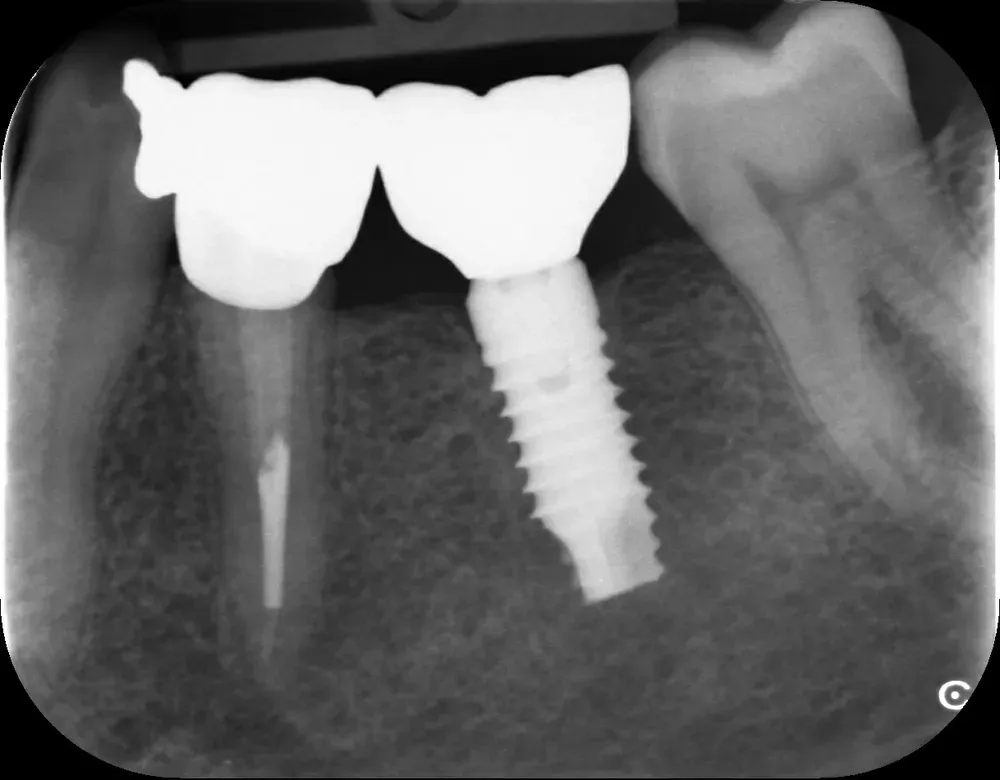

Gli impianti transmucosi devono essere posizionati transmucosi, soprattutto se hanno connessioni non particolarmente “sigillanti”. Usati in tal guisa, sono perfetti. Le immagini che seguono dimostrano che i transmucosi, se posizionati al giusto livello verticale, causano ZERO riassorbimento della cresta ossea.

La regola dei 4mm di Linkevičius ci viene in aiuto per stabilire la posizione verticale che protegge l’impianto dal riassorbimento osseo, sempre nel caso di connessioni affidabili dal punto di vista batteriologico. Nelle prossime immagini, dei monconi protesici relativamente lunghi su impianti a connessione conica, testimoniano l’ottimo risultato reale di questo concetto, con impianti perfettamente integrati e privi di infiltrazione infiammatoria, anche in condizioni ossee impegnative.

Per concludere il confronto tra le varie connessioni, l’immagine che segue è una radiografia con due impianti affiancati: un tissue-level ben posizionato fatto da un collega anni addietro e un impianto a connessione conica in posizione infracrestale con abutment della corretta lunghezza per il caso. Il secondo è un mio caso. È interessante notare come il cono dello spazio biologico sia identico. Se ben posizionati, tutti gli impianti funzionano egregiamente (l’impianto più vecchio inizia a soffrire un pochino, ma questa è un’altra storia).